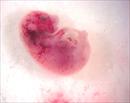

| Mutant 2459-006-1 (E16.5) presents with hydrops and ptechiae | b2b2459Clo/b2b2459Clo | C57BL/6J-b2b2459Clo |

| Mutant 2459-003-2 (E14.5) was harvested with hydrops and abnormal vasculature | b2b2459Clo/b2b2459Clo | C57BL/6J-b2b2459Clo |